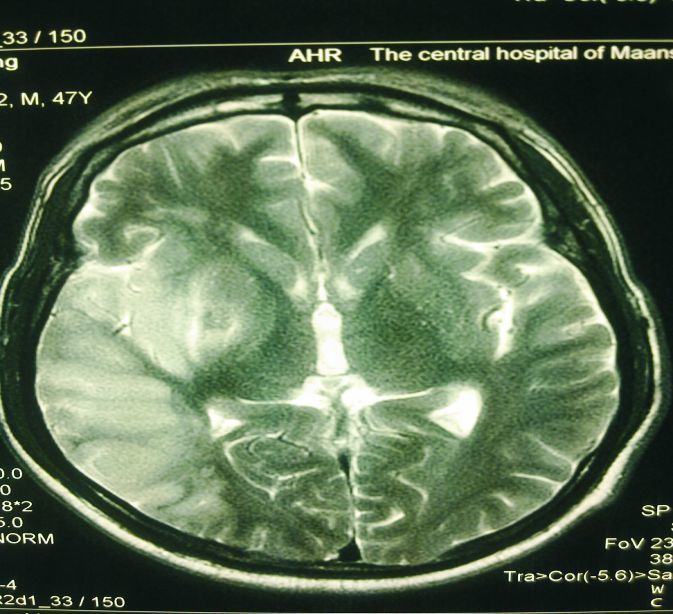

影像学检测(头颅MRI及股四头肌磷谱):右侧股四头肌Pi/PCr0.125(premotion 1)、0.147(premotion 2)、0.136( aftermotion)。①侧颞枕叶、左侧颞叶外缘及两侧海马肿胀,伴轻度细胞毒性水肿;②两侧额顶叶、侧脑室旁脱髓鞘改变(Fezakas Ⅰ级);③脑脊液、两侧底节区均可见乳酸峰显示,左侧海马NAA轻度降低(神经元功能及数量下降)(图 3、4)。

| 图 3 影像学检测1 |

脑影像学检查对MELAS的临床诊断具有重要辅助作用。本例患者的MRI及MRS检查:①左侧颞枕叶、左侧颞叶外缘及两侧海马肿胀,伴轻度细胞毒性水肿;②两侧额顶叶、侧脑室旁脱髓鞘改变(Fezakas Ⅰ级);③两侧底节区均可见乳酸峰显示,左侧海马NAA轻度降低(神经元功能及数量下降)。MELAS 综合征脑MRI的特点为患者两半球后部多发卒中样异常信号,病变不按血管解剖分布,累及皮层和皮层下白质,可见皮层的层状异常信号。有人认为这种皮层和皮层下多发性层状异常信号是MELAS的特征性改变,具有重要诊断意义。肌肉活检病理学检查是诊断MELAS的重要手段。到1984 年Pavlakis等首先报道本病。人们对MELAS的肌肉病理学改变认识越来越深入,肌纤维中发现RRF 是诊断线MELAS的重要依据。肌肉活检:在肌膜下或肌纤维内可见不规则红色颗粒状改变(RRF),系异常线粒体堆积的一种表现。本例患者行股四头肌活检发现在肌膜下或肌纤维内可见RRF的存在,是诊断的有力证据。